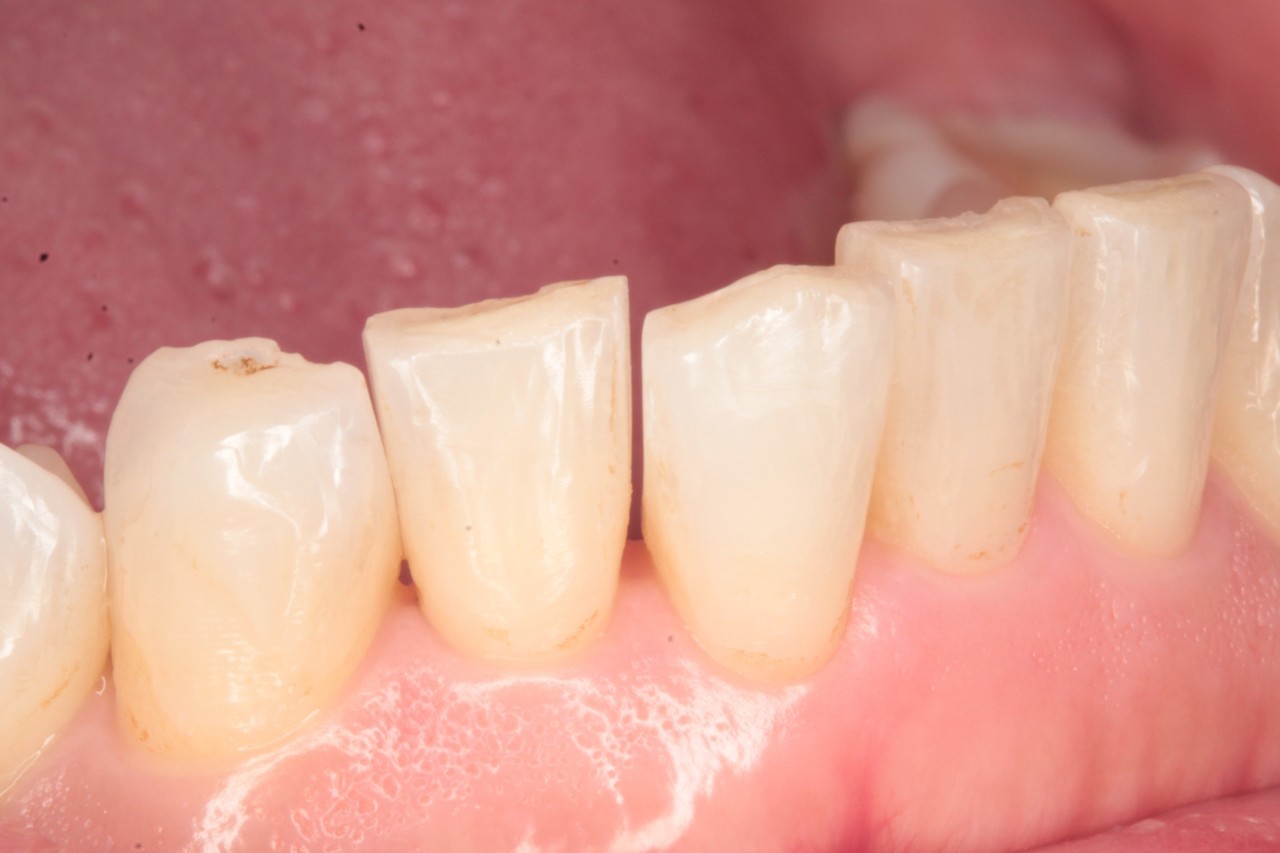

今回の症例は写真のように上の中心から2番目の歯が左右とも奥に入り込んでいてかなりスペースのない状態でした

②IPRとは?

動画のようにIPRとは、薄く歯間を削り、スペースを得る方法です(1か所最大0.5㎜)。きちんと処理をすれば、痛みも害も出ません。むしろ、歯が強化されて虫歯になりにくくなる、という研究データすらあります。